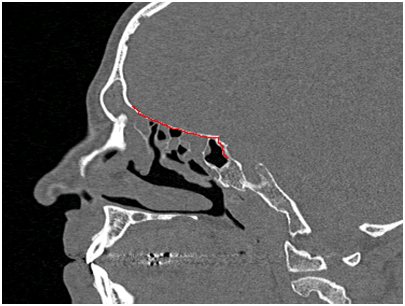

The rationale behind the preoperative treatment is the reduction of inflammation which will lead to less bleeding during the operation and therefore to more accurate dissection of the tissues.7 At the same time, the shrinkage of polyps and the reduction of mucosal edema will render the nasal cavities more accessible during endoscopic examination. It is now time for a second evaluation of the nose to decide in which nostril we will apply the dermoplasty technique. In the first three cases dermoplasty was applied in both nostrils. This resulted in a prolonged operation becoming cumbersome for the surgeon and dangerous for the patient. Then we decided to apply dermoplasty unilaterally planning to return to the contralateral nostril at a second stage. Our criterion as on which nostril to apply dermoplasty is the accessibility of the axilla of the middle concha which results in unobstructed insertion of the endoscope and the instruments in the middle meatus. Another effect of the preoperative treatment is the ability to study the anatomy of the ethmoidal labyrinth. At the end of the regimen the patient is submitted to a computed imaging (CT) of the nose and paranasal sinuses. The study of the CT will provide us with information about the anatomy of the ethmoidal complex and any areas of danger like the optical nerve, the internal carotid artery etc. The study of the CT will also permit us to estimate the surface and the contour of the skin graft needed. The radiologist will measure the distance between the posterior end of the frontal ostium and the sphenoid sinus (including its roof) in the sagittal plane (Figure 1) and then he/she will proceed to the coronal plane to measure the sum of the length of the lamina papyracea, the fovea ethmoidalis and the middle or upper concha at ten points moving from the posterior rim of the frontal ostium to the sphenoid sinus (Figure 2). The combination of these measurements will give the surface and the contour of the skin graft needed.

Figure 2 Consecutive measurements at the coronal plane.